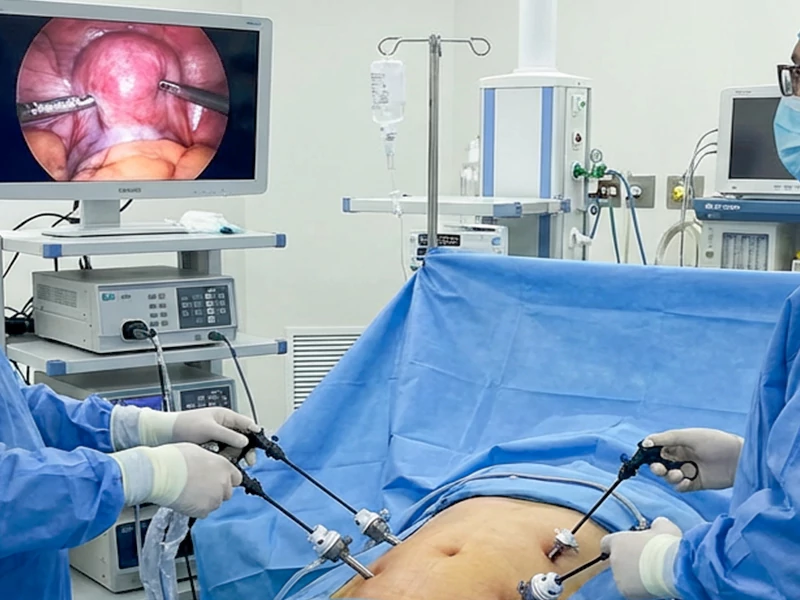

صفر تا صد لاپاراسکوپی رحم + فیلم اتاق عمل

لاپاراسکوپی رحم (Laparoscopy of the uterus) یکی از روشهای کم تهاجمی در جراحی است که برای تشخیص و درمان مشکلات